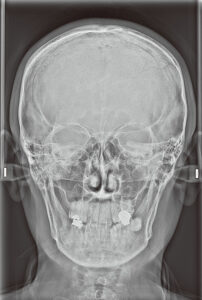

セファロで分かること(矯正・成長・噛み合わせ)

セファロは矯正で使う検査で、骨格・歯の傾き・上下顎の位置関係を規格化された条件で評価できます。

• 上下顎の位置関係

• 歯の傾きや突出感

• 成長の方向性(小児矯正の評価です)

• 気道や姿勢との関連のヒント(必要に応じて評価します)

【セファロ画像(例)】

骨格と歯の位置関係を評価し、設計の根拠にします。